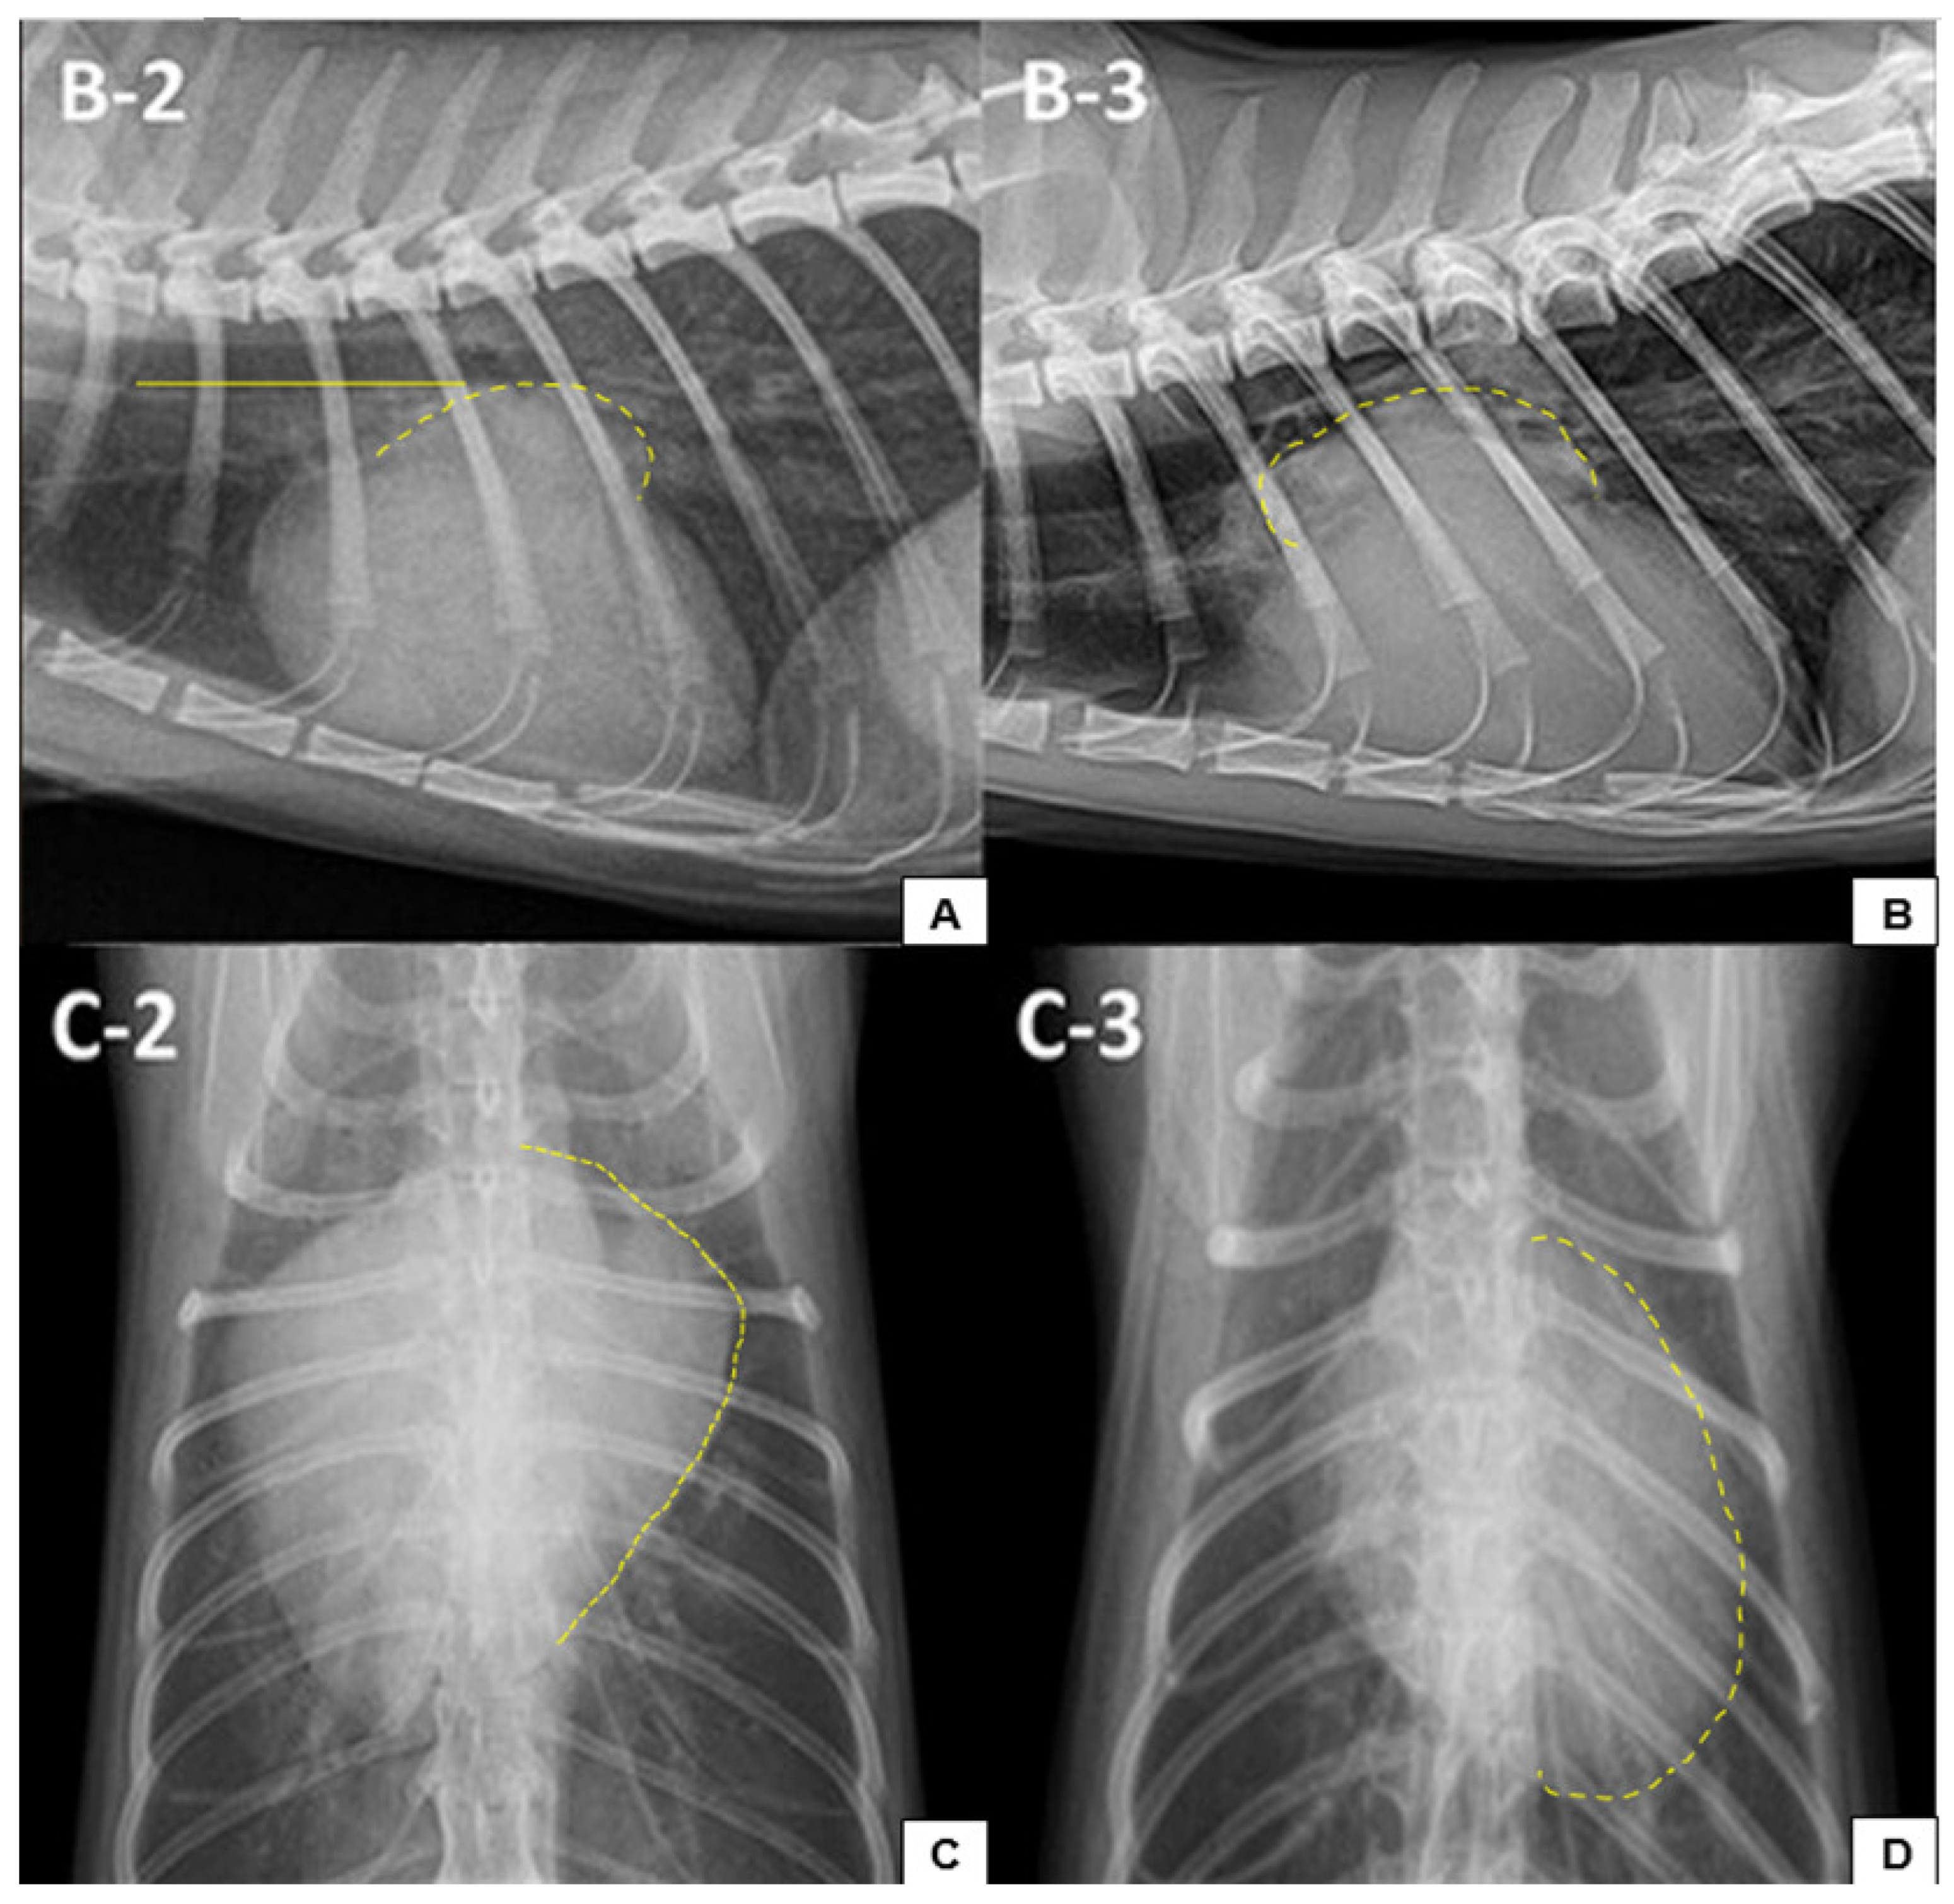

7.2.1. Thoracic Radiographs

- Kim, S.; Lee, D.; Park, S.; Suh, G.H.; Choi, J. Radiographic findings of cardiopulmonary structures can predict hypertrophic cardiomyopathy and congestive heart failure in cats. Am. J. Vet. Res. 2023, 84, ajvr.23.01.0017. [Google Scholar] [CrossRef]